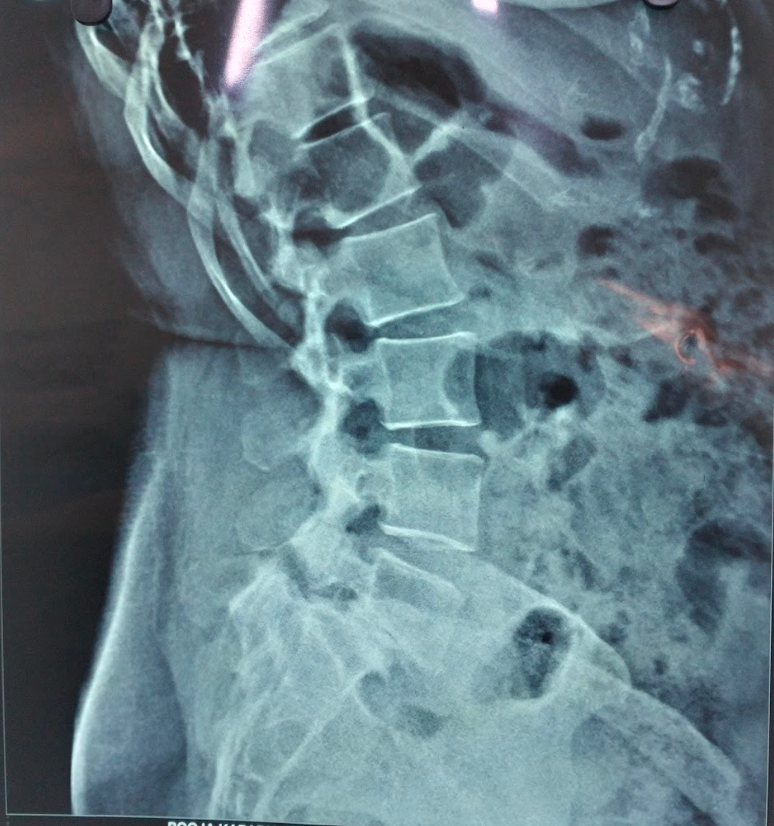

- X-rays – Initial screening (may miss early stage)

Spondylolysis is a condition characterized by a stress fracture or defect in the pars interarticularis, a small but critical portion of a vertebra. It most commonly affects the lower lumbar spine, especially the L5 vertebra, and is a frequent cause of back pain in adolescents, athletes, and young adults.